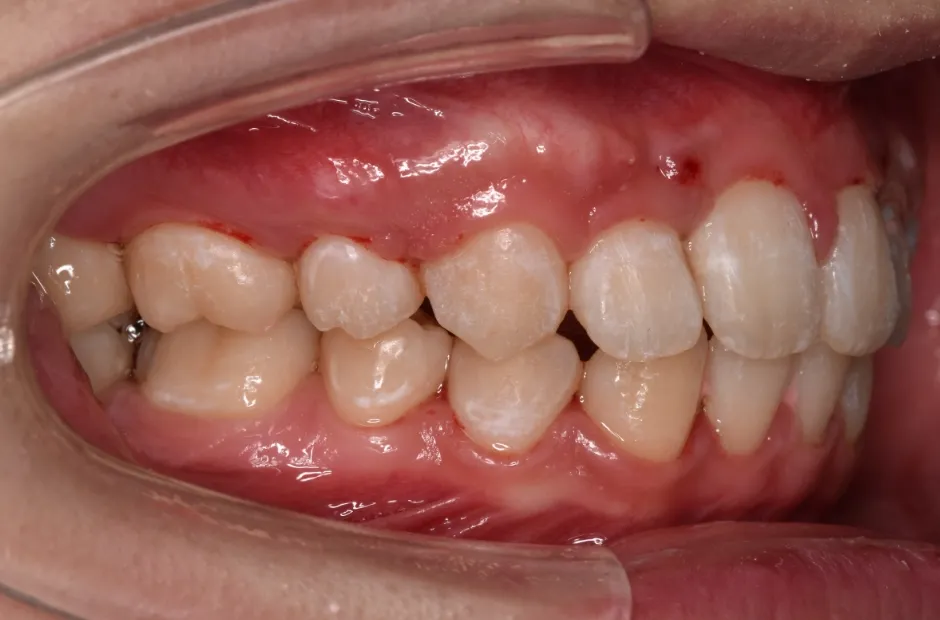

すきっ歯

| 診断名・主訴 | すきっ歯 |

|---|---|

| 年齢・性別 | 22歳・女性 |

| 治療期間・回数 | 2年半 30回 |

| 治療に用いた主な装置 | アンカー |

| 抜歯部位 | なし |

| 治療費 | 100万円(税抜) |

| リスク・副作用 | 装置による違和感・疼痛・歯肉退縮・歯根吸収・虫歯のリスクなど |

治療前

治療中

治療後